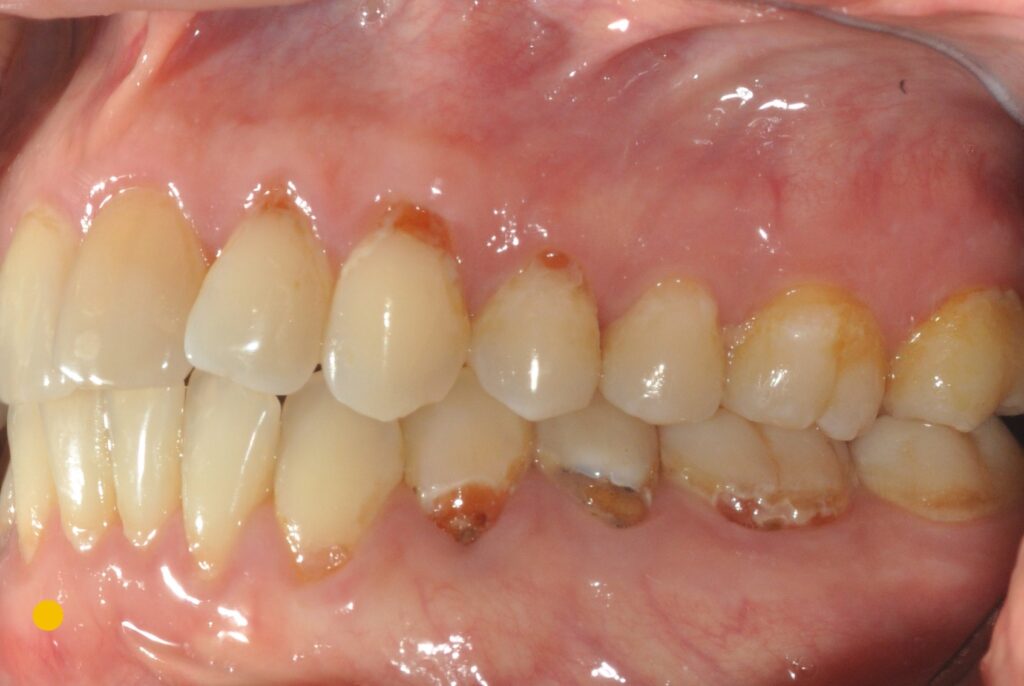

בתמונה כאן משמאל שיניים של מטופל, שהגיע אלינו לפני מספר שנים. הוא עשה הרבה דברים כדי לטפל ולטפח את הבריאות שלו , אבל ראה שזה בעצם גורם לו ליותר ויותר בעיות וכשהוא הגיע אלינו נראו חורים מאוד עמוקים בצוואר השן, דבר שמעיד על דרגת סיכון מאוד גבוהה לעששת.

מצב זה נובע בד”כ ממספר בעיות, שחלק ניכר מהן קשור לרמה גבוהה של קורטיזול בדם. כאן אנחנו לומדים כיצד לאזן אותו ביעילות גבוהה יותר. בפרק הבא, אלמד אתכם ממה זה נובע ומה עוד ניתן לעשות כדי לשפר את הבריאות.